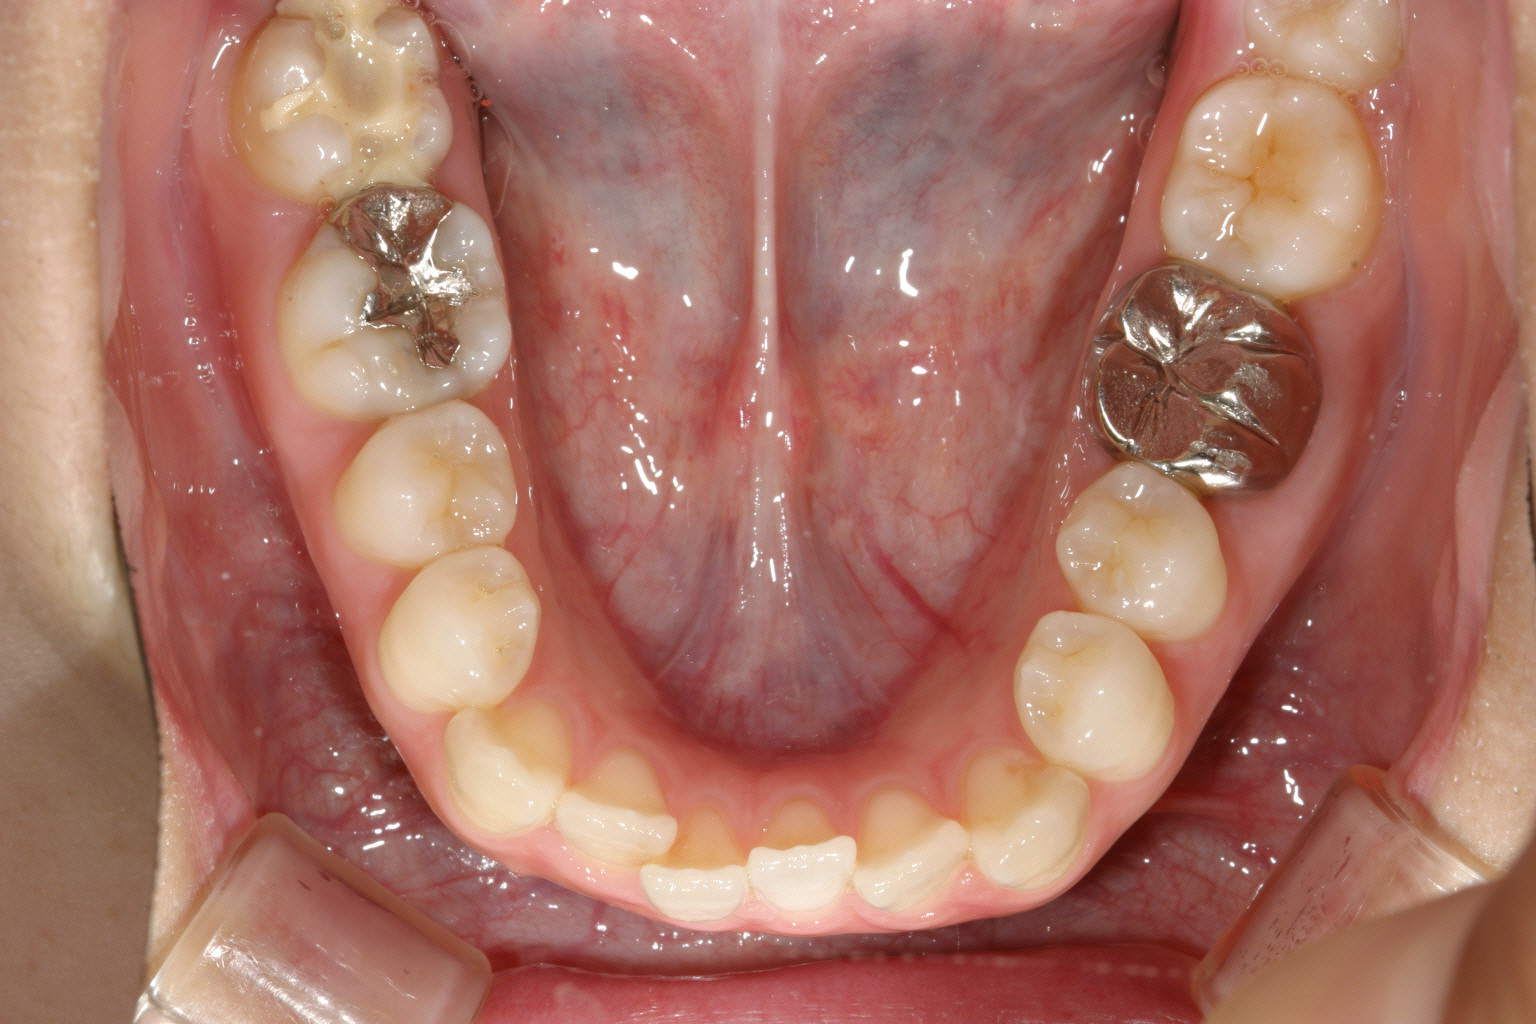

下顎も上顎と同じく犬歯間幅径が狭く叢生になってます。

下顎も半年経つとかなり綺麗に並んでいます。

下顎もバッチリです。